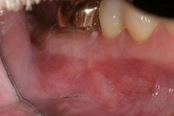

Mid-root crack repair:

Dye used to verify the crack

Crack removed

Filled with GeristoreThe patient was eating and bit down, felt and heard a “pop.” The tooth had cracked in the middle of the root. The tooth helps hold the patients partial in place and did not want to lose the tooth. The crack was removed with the laser and then restored.

The photograph is 2 months after the crack repair. The area looks like nothing was done (no redness, no scarring, etc.) and the tooth is there helping to hold the partial denture.